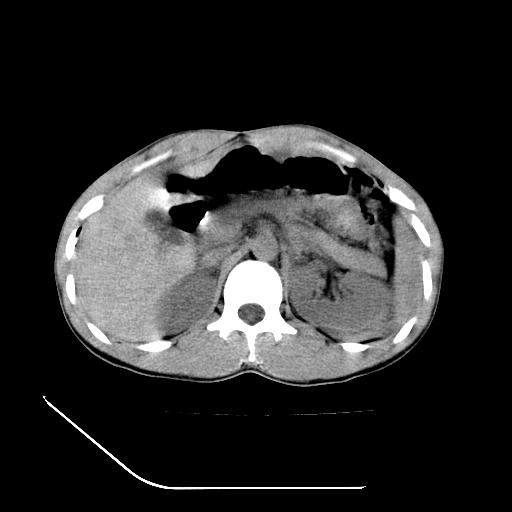

m-25y 高空堕落 12 月5号

12月7号病人尿量200ml/24h 急查双肾ct

支持:1、左肾挫裂伤并肾周血肿;

2、少量腹水;

3、左肾旋转不良;

4、反射性肠淤张。

反射性肠郁张是指许多原因造成肠道吸收气体和液 功能障碍,也可造成分泌功能与动力的障碍,以致肠道内有过量的气体和液体潴积,有时只有过量的气体潴积。肠道较舒张,但不扩大,或有部分肠道轻度的扩大,这种情况叫做反射性肠郁张 ,这个病人的肠管扩张太明显了。

提示有肠梗阻的可能性?

综上所述,考虑1:左肾挫伤并包膜下血肿2:少量腹腔积液3:肠梗阻的可能

除了1:左肾挫裂伤并肾周血肿;

2:少量腹水

第二次ct检查后:临床医生腹水穿刺后考虑肠系膜动脉破裂,后实行剖腹探查:于空肠距离十二指肠90cm处发现肠管破裂,破裂口较小;修补后关腹。

第4点我到考虑为高空坠落后引起的动力性肠梗阻.

结果收到,谢谢楼主,另外反过来看这个地方是不是游离气体影

病人尿量200ml/24h,是否用反射性肠淤张可以解释。